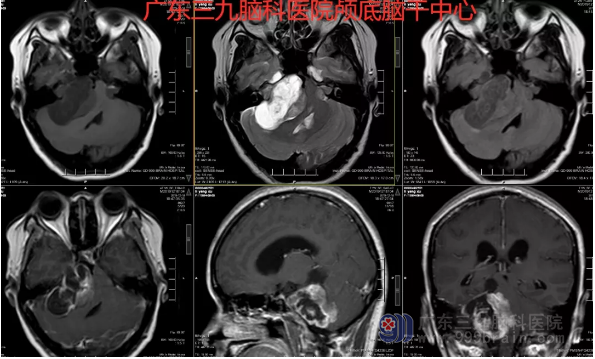

图1:术前MR示侧横窦及乙状窦交界处局部信号减低、缺失,考虑为肿瘤压迫所致